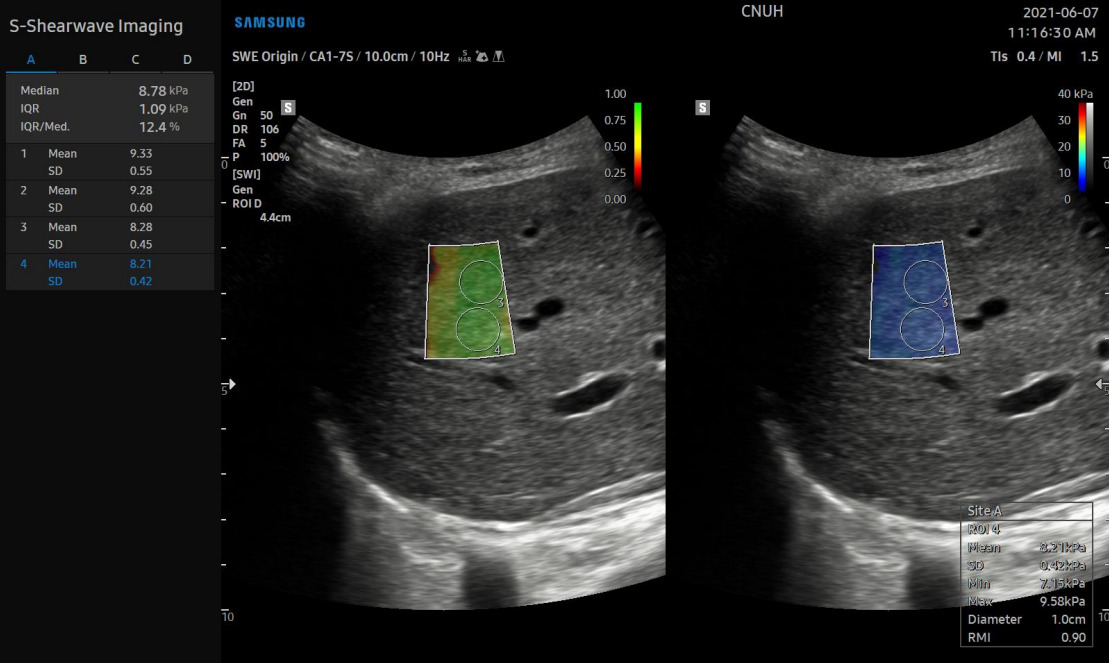

Особенности метода делают SWE портативным и выполнимым в различных клинических условиях. Так, современные ультразвуковые системы способны проводить эластографию печени (сдвиговой волны) с высокой точностью. Например, в УЗ системах Samsung функция эластографии называется 2D-SWE (S-Shearwave Imaging). Было установлено, что пороговые значения для диагностики начального фиброза, прогрессирующего фиброза и цирроза печени, составляют 6,82 kPa при ≥ F2, 8,63 kPa при ≥ F3 и 9,66 kPa при F4 соответственно. Данные значения актуальны только для систем Samsung..jpg?1683706893287)